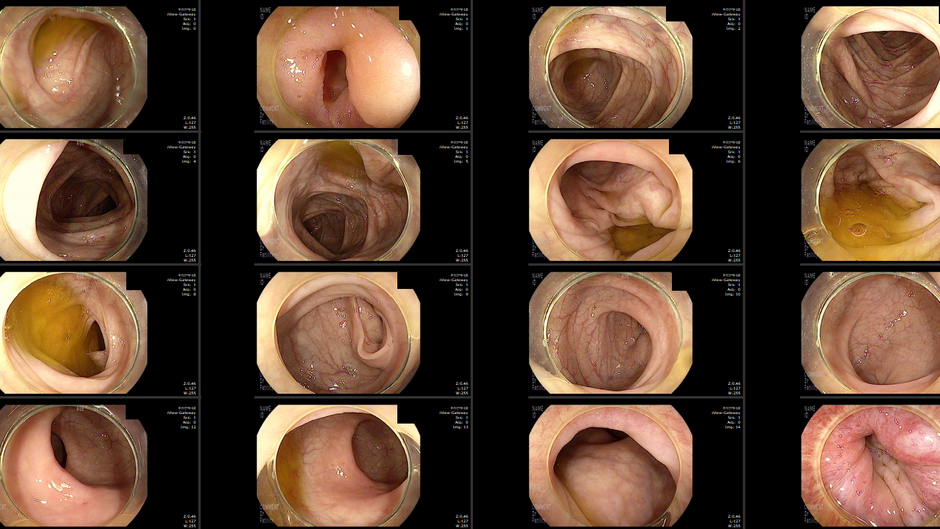

80대에서 진행성 선종 - 동대문구 답십리, 장안동, 우리안애 우리안愛 내과

80대 초반 남자 19년도 초진, 당시 3~4년전 용종 기왕력 확인 후 대장 내시경 상담함, 당뇨/혈압 투약중으로 아스피린등 약제 확인 예정이었음 21년 어르신 독감 접종 24년 내원 먹으면 구역감.. 식후 미식거린다. 구토도 2회...